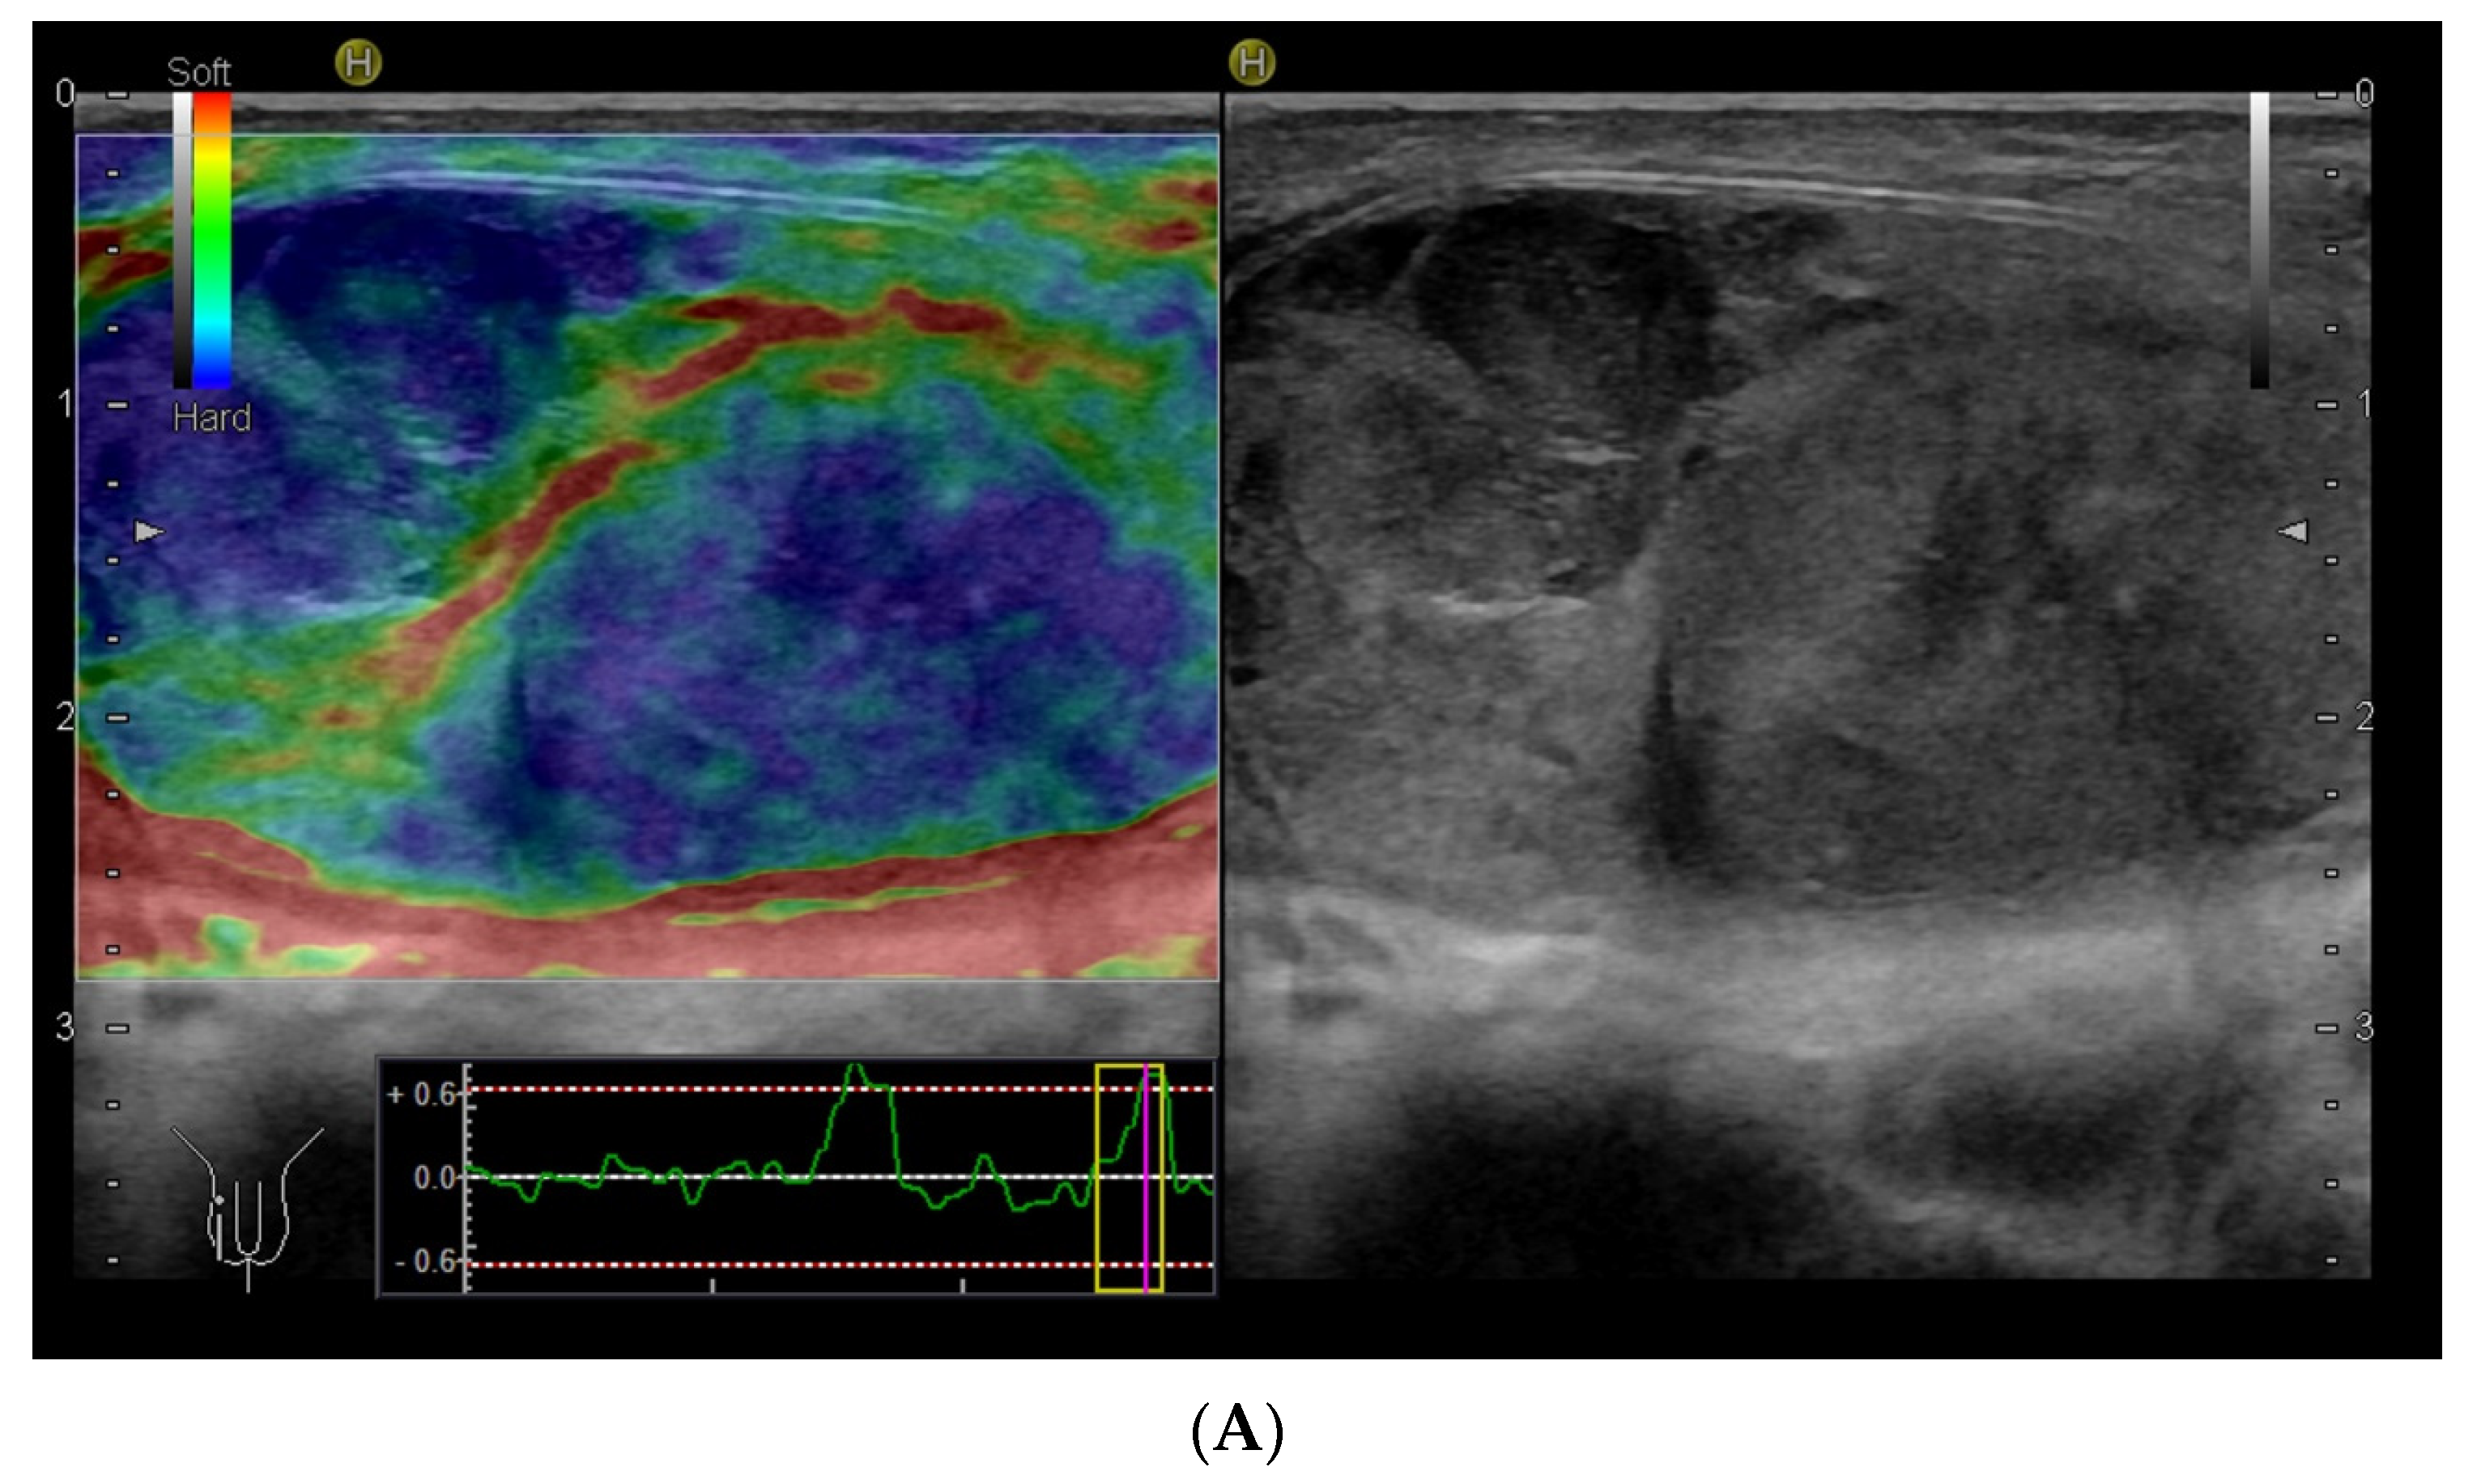

4.2. Scrotum Anatomy and the Scanning Technique

Within the scrotum, the two testicles are divided by a septum. Each testicle is oval-shaped and typically measures 4 cm in length, 3 cm in width, and 2 cm in height [64]. The anatomy of the testicles can be seen in Figure 6C, and an ultrasound image including SE is shown in Figure 6A,B. A high-frequency linear transducer is typically the preferred and best choice, but in cases with an enlarged scrotum, a curved array transducer may be a better choice.

Figure 6.

Ultrasound images of a 39-year-old male. The indication for ultrasound investigation was suspected orchitis or malignancy. The patient experienced pain in the right testicle for more than 2 days. The patient was seen in the emergency room for assessment of epididymitis and started treatment with ciprofloxacin. There was no improvement with treatment, and the right testicle became more tender and swollen. The ultrasound showed no signs of epididymitis (A). The right testicle (left side of the figure shows the elastogram, and B-mode is seen on the right side). The testicle revealed a right-sided tumour, which appeared highly suspicious using elastography (B). The B-mode image, showing a tumour (C). B-mode image of the left testicle, showing normal tissue (The pathology showed a seminoma testicular tumour with 2% of choriocarcinoma. The patient underwent surgery for removal of the right testis.